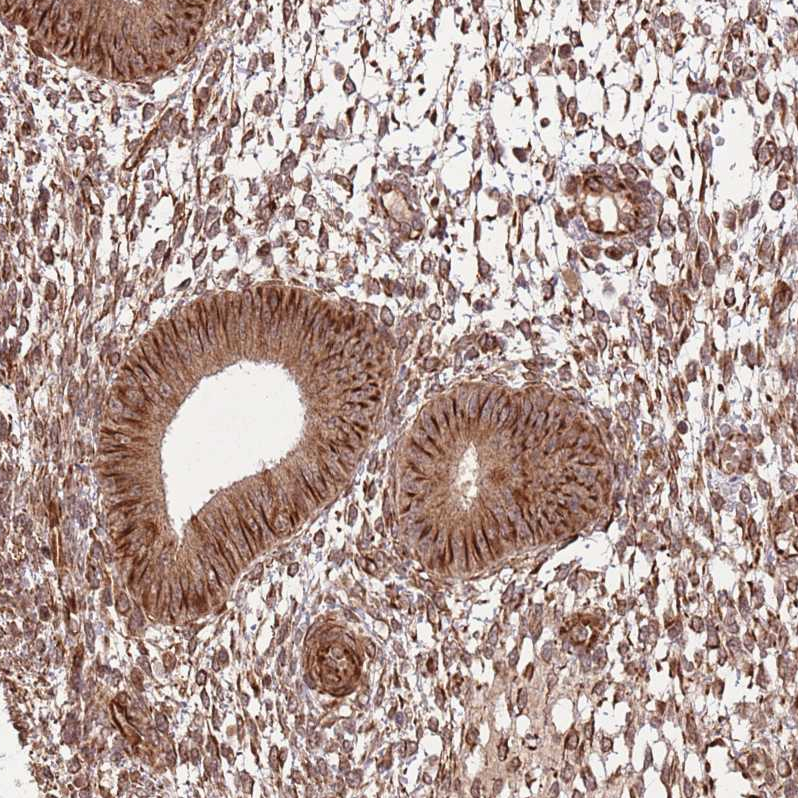

Immunohistochemical staining of human testis shows strong cytoplasmic positivity in cells in seminiferous ducts.